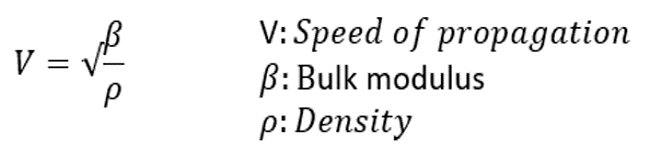

Propagation Speed

Theoretically, the speed of propagation is the speed at which sound travels through a particular organ and is dependent on the elastic property and density of the organ. The harder the tissue, the faster the speed of propagation. The average speed of sound in soft tissues such as the chest wall and the heart is 1,540 meters per second.